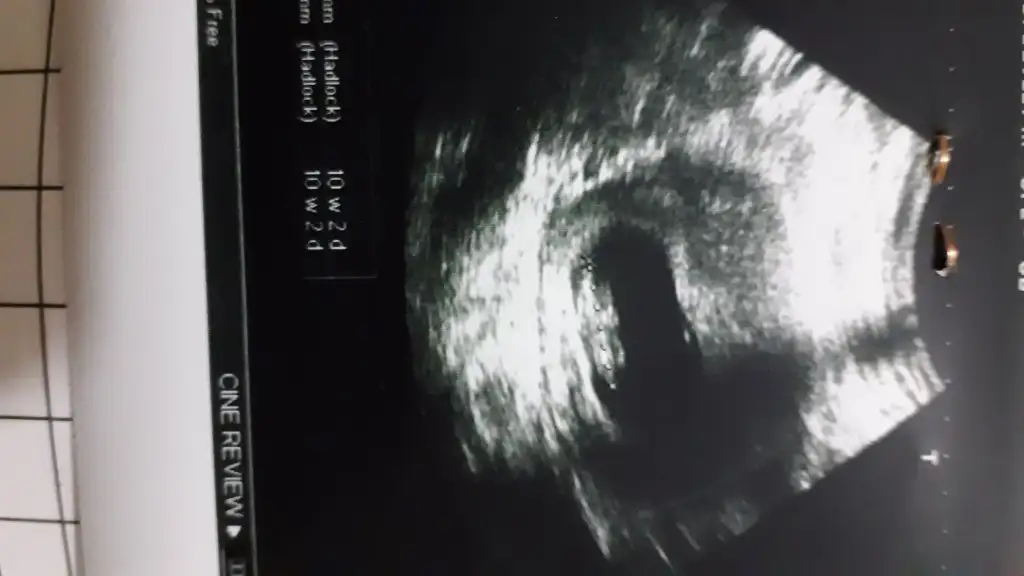

2020 Haziran Anneleri Gebelik, Ultrason, Testler, Gebelik Takibi